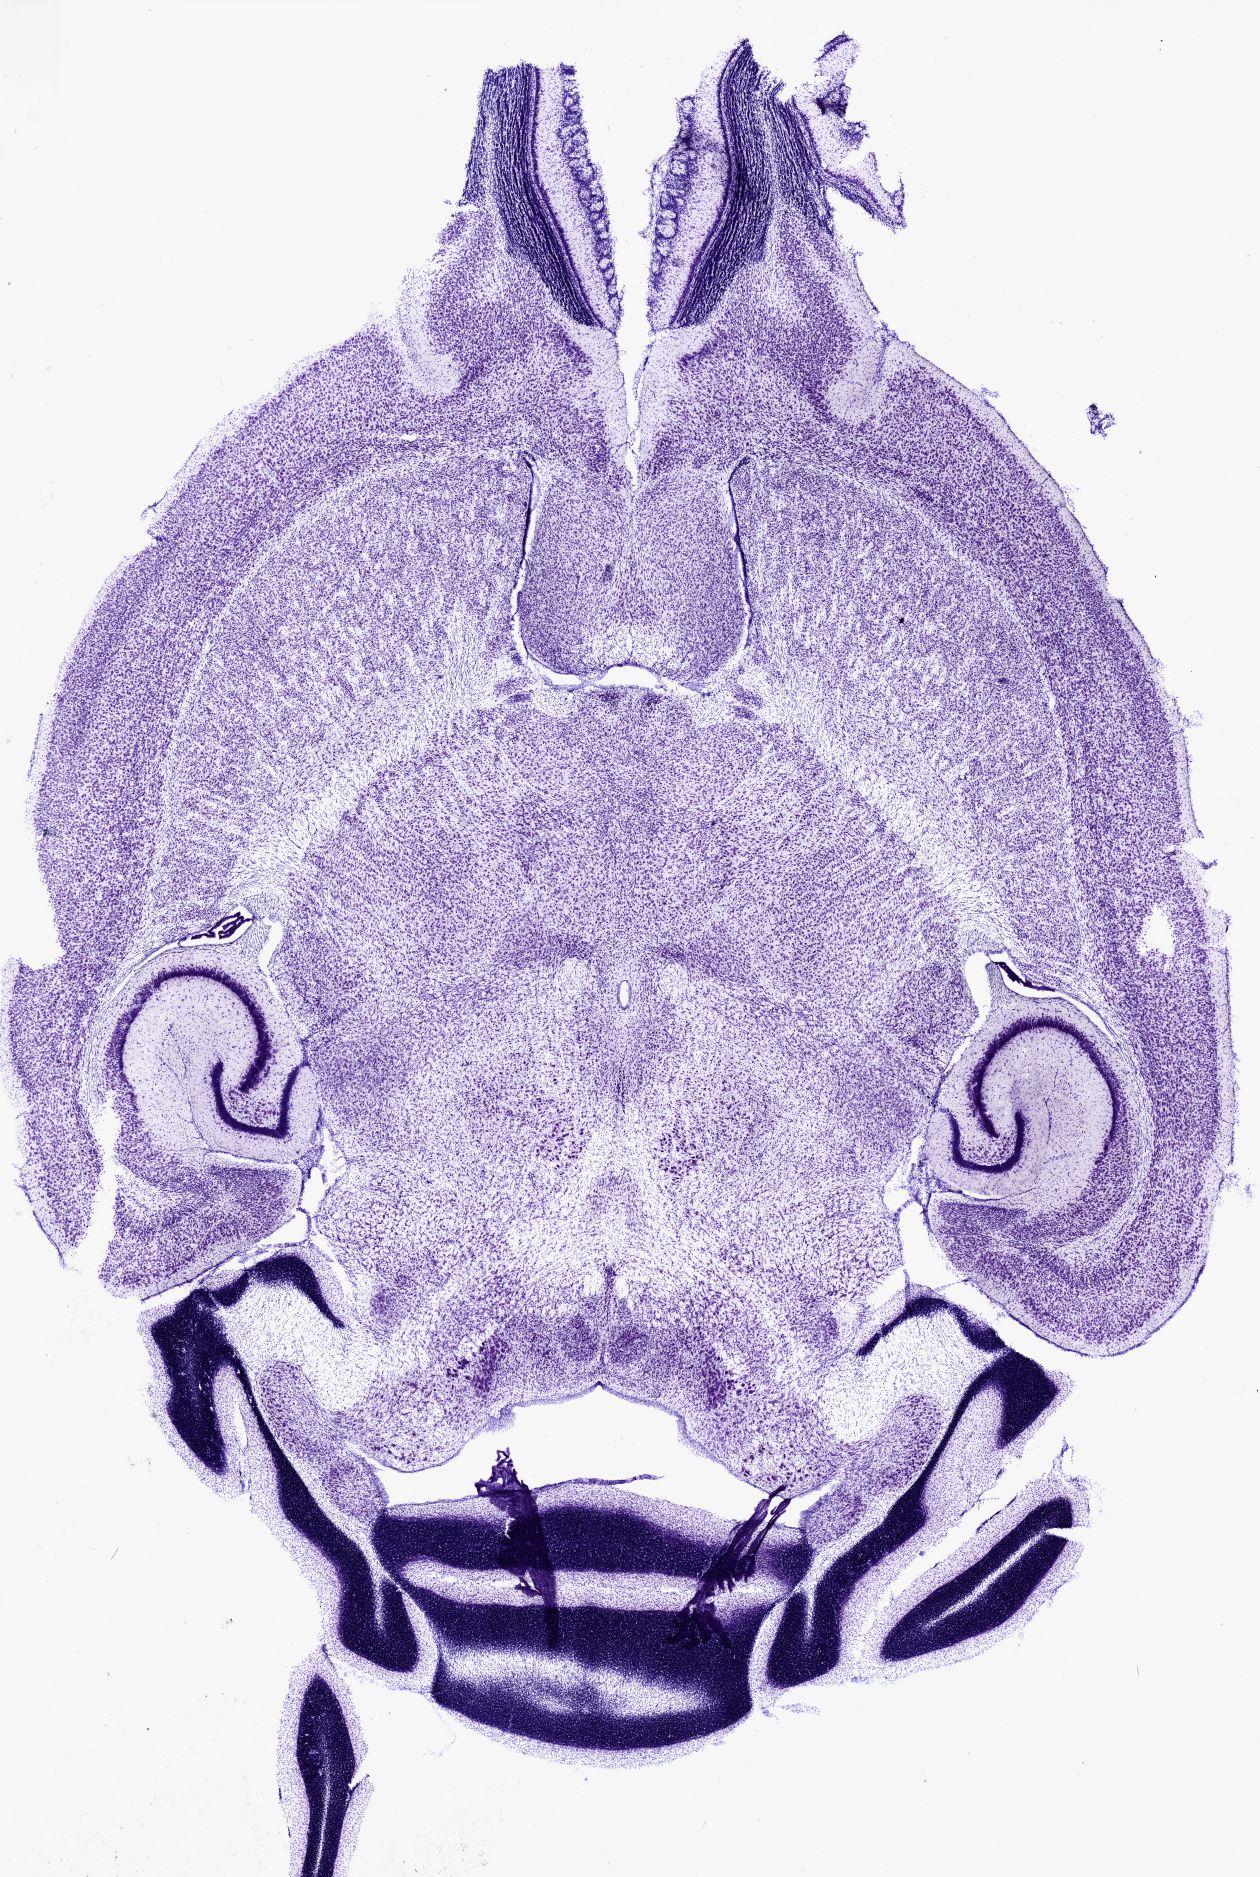

Datasets -> Mus Musculus -> Nissl, horizontal, histo, Whole-Brain, adult

[ Metadata ]   ·   Source: Shawn Mikula

Displaying Sections 41 thru 67 of 67 Sections for this Dataset